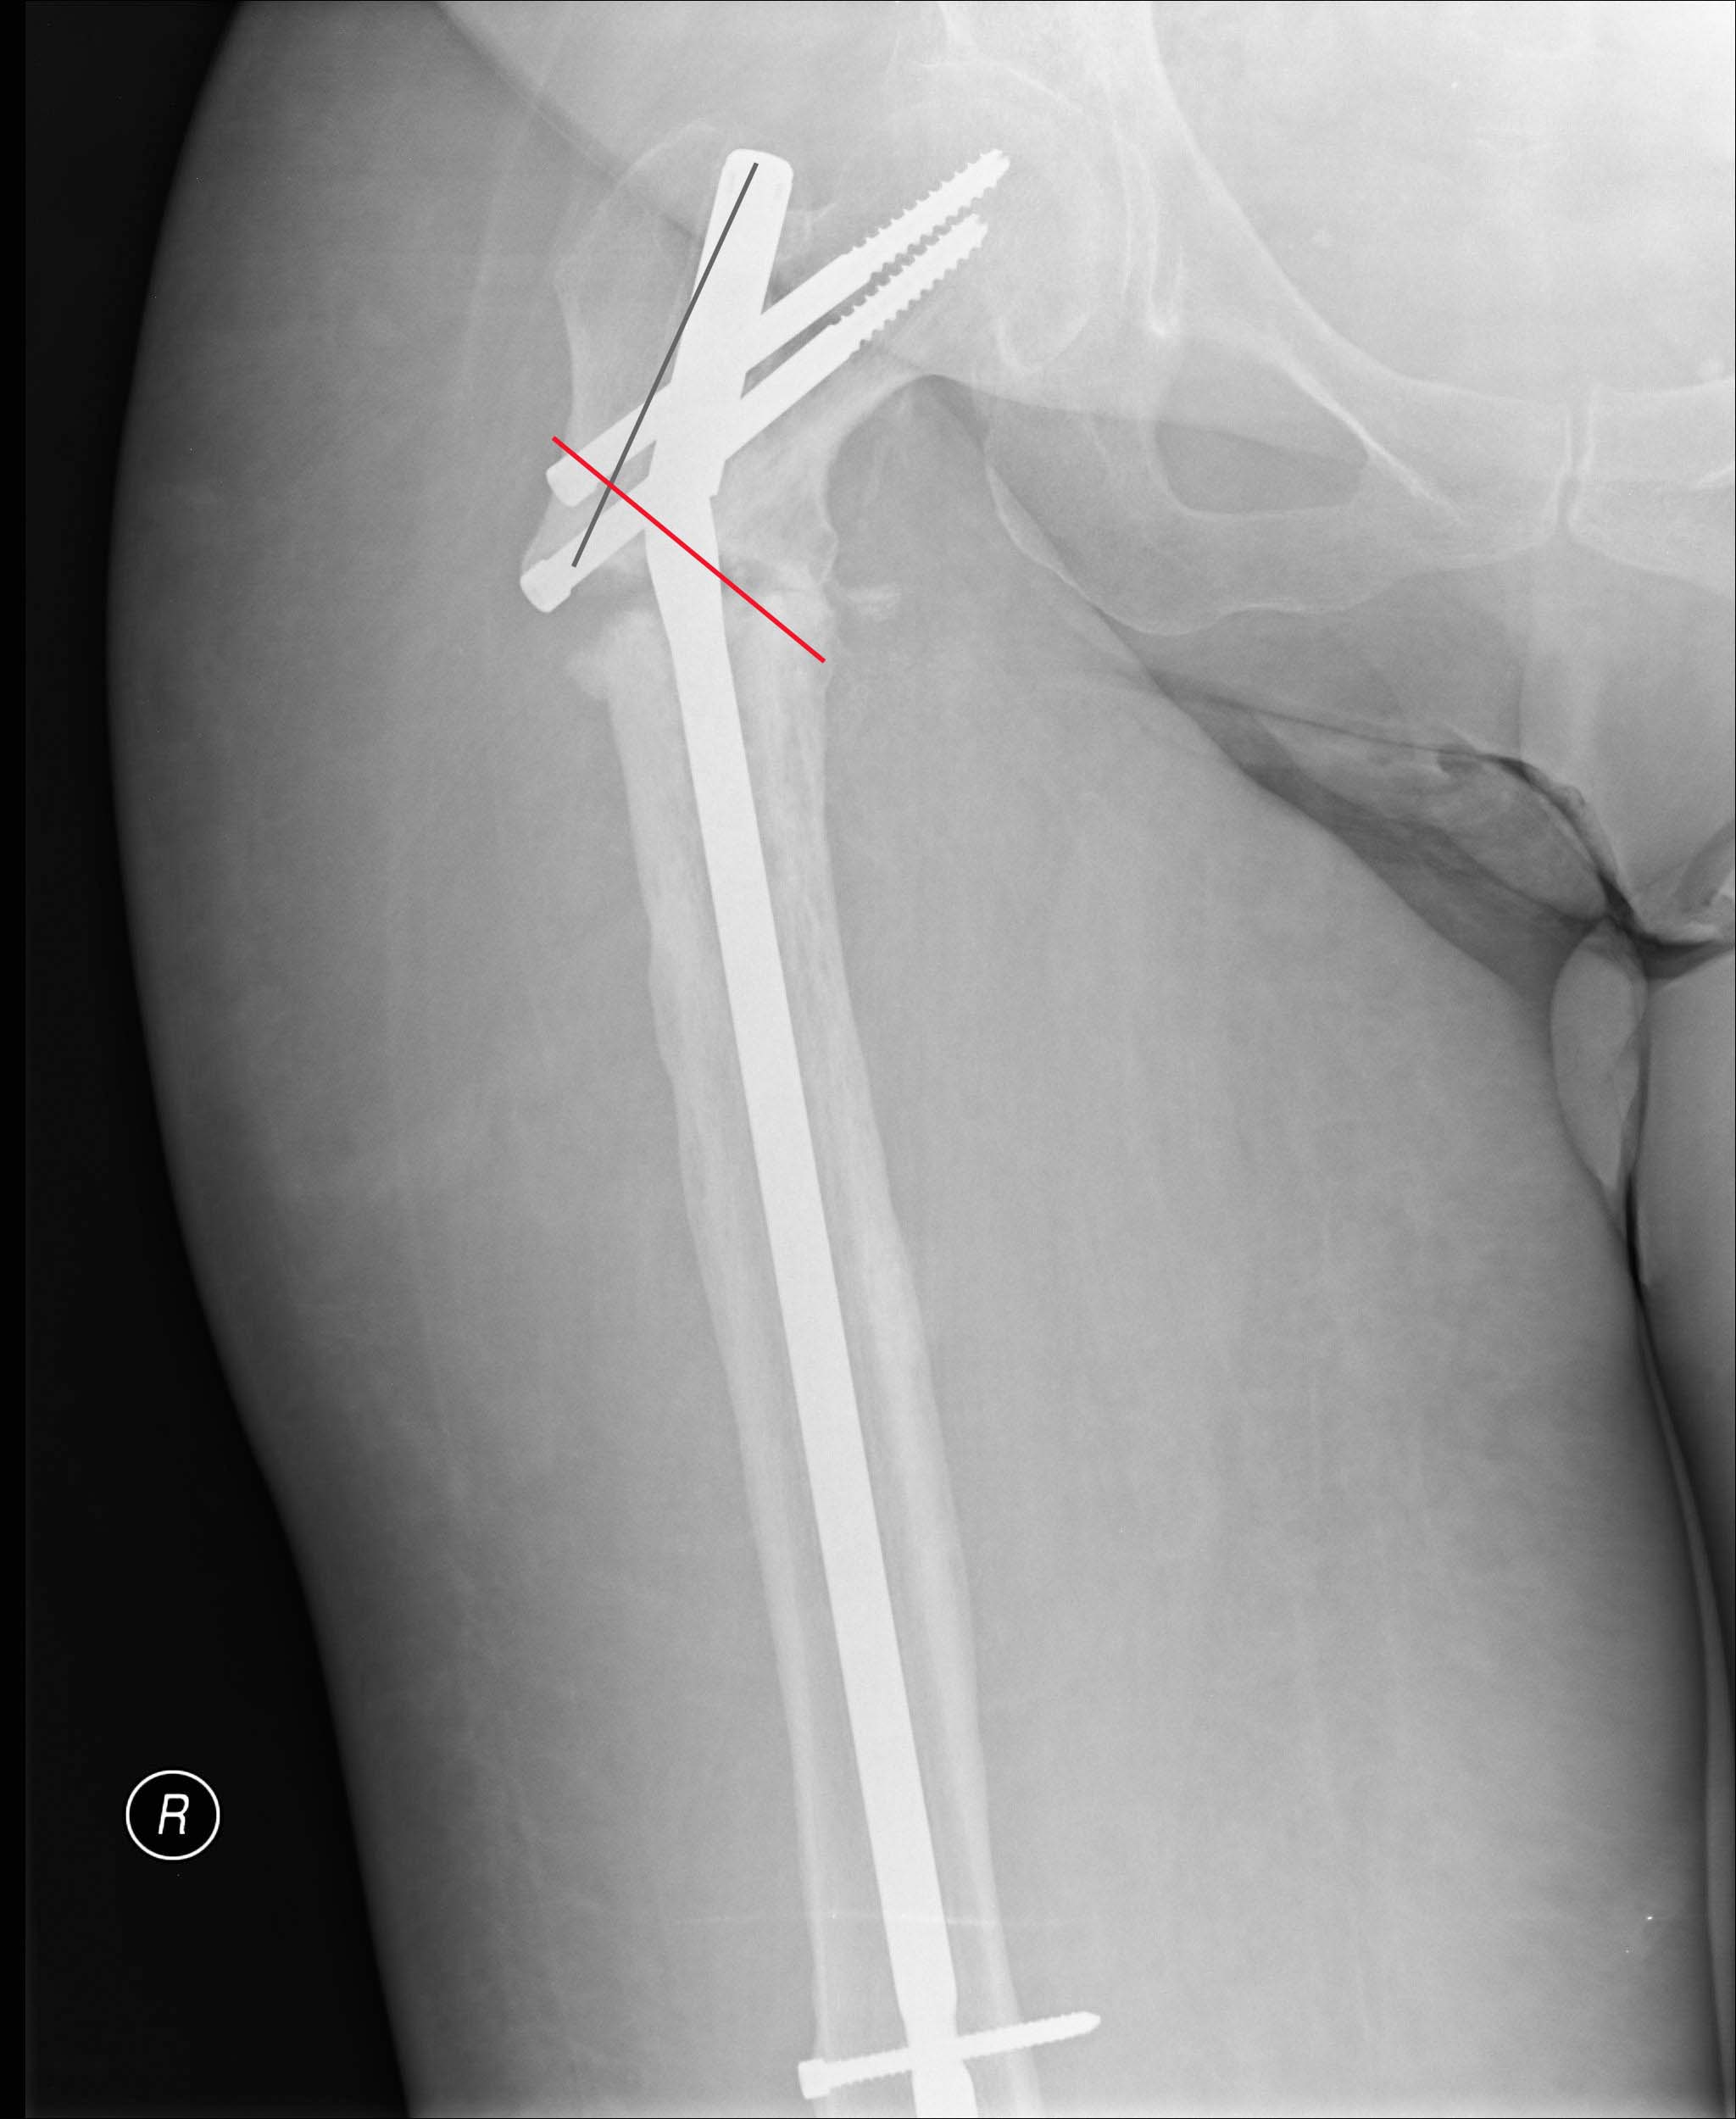

åÓÌÉ ÐÏÓÌÅ ÕÄÁÌÅÎÉÑ ÐÏÄ×ÉÖÎÏÓÔØ ÈÏÒÏÛÁÑ, ÔÏ ÚÁËÒÙÔÏ ×ÐÒÁ×ÉÔØ. åÓÌÉ ÎÅ

ÕÄÁÅÔÓÑ ×ÁÌØÇÉÚÉÒÏ×ÁÔØ Ó ÇÉÐÅÒËÏÒÒÅËÃÉÅÊ, ÔÏ ÍÏÖÎÏ ÓÄÅÌÁÔØ ÞÒÅÓËÏÖÎÕÀ

ÏÓÔÅÏÔÏÍÉÀ ÞÅÒÅÚ ÎÅÓÒÁÝÅÎÉÅ. îÁÄÏ ÎÅ ÐÒÏÓÔÏ ×ÏÓÓÔÁÎÏ×ÉÔØ ÏÓØ, Á Ó

ÇÉÐÅÒ×ÁÌØÇÕÓÏÍ, ÔÏ ÅÓÔØ × ÃÅÎÔÒÁÌØÎÏÍ ÏÔÌÏÍËÅ ÎÏ×ÙÊ Ç×ÏÚÄØ ÐÒÏ×ÅÓÔÉ ÉÚ ÔÏÊ

ÖÅ ÔÏÞËÉ ×ÈÏÄÁ, ÎÏ ÄÁÌØÛÅ - ÌÁÔÅÒÁÌØÎÅÅ ÉÍÅÀÝÅÇÏÓÑ ËÁÎÁÌÁ. ôÏ ÅÓÔØ ××ÅÓÔÉ

Ä×Å ÓÐÉÃÙ ÓÐÅÒÅÄÉ ÎÁÚÁÄ × ÓÔÁÒÙÊ ËÁÎÁÌ, É ÐÒÏÄÅÌÁÔØ ÌÁÔÅÒÁÌØÎÅÅ ÎÏ×ÙÊ. îÁ

ÐÒÉÌÏÖÅÎÎÏÊ  ËÁÒÔÉÎËÅ ÐÏËÁÚÁÎÙ ÐÒÁ×ÉÌØÎÏÅ ÐÏÌÏÖÅÎÉÅ Ç×ÏÚÄÑ É ÌÉÎÉÑ

ÏÓÔÅÏÔÏÍÉÉ.